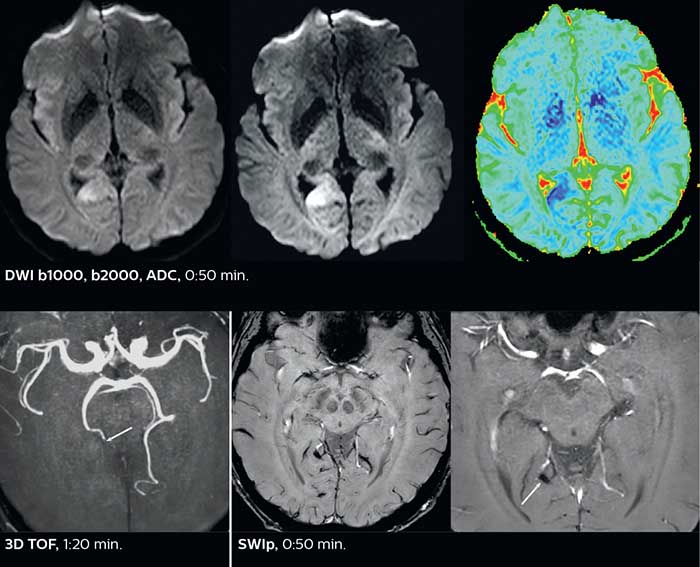

Dr. Savatovsky appreciates the improvements and flexibility that Elition with Compressed SENSE and MultiBand SENSE provides, particularly for stroke patients. “For stroke, it allows us to cut about 5 minutes off of our stroke protocol, or to keep the same acquisition time and get more insights.” The ability to perform more sequences can help in making a swift and confident diagnosis. “For example, our stroke cases usually include the regular sequences that every center does (b1000 diffusion, FLAIR, time-of-flight angiography), but we also image supra aortic vessels, and we can replace a gradient echo sequence with a fast 50-second susceptibility-weighted sequence, and all of this doesn’t add much time. because all the regular sequences are accelerated on Elition.” “The time savings with Compressed SENSE and MultiBand SENSE make it easier to add sequences to give us additional insights. Depending on the context and the first results, we might add a DSC perfusion to assess the ischemic penumbra, an ASL perfusion to help find an alternative cause in case of normal diffusion, or add a high-resolution T1 sequence for a stroke patient, to quickly assess wall imaging in emergency cases. The additional sequences can help improve patient management, because we can already consider some alternative diagnoses if the morphological MRI is normal.”

This is an example of acute ischemic stroke with distal occlusion of the right posterior cerebral artery. Note the improved visibility of the ischemic territory on the diffusion weighted image with high b-value. The 3D FLAIR shows a distal PCA occlusion. The fast SWIp depicts the thrombus on the isolated second echo image. The total scan time (including SmartBrain, preparations and a fast 3D T1w TSE Gd) is 8:00 minutes.